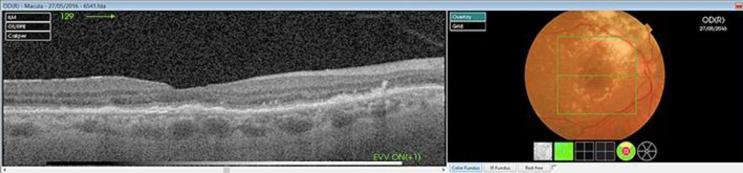

息肉样脉络膜血管病变(PCV)是新生血管性年龄相关性黄斑变性的一种亚型,其特征是具有动脉瘤样息肉样脉络膜血管病变的异常分支血管网络。PCV在亚洲人群中比在白种人中更普遍,这可能解释了其在西方国家诊断不足的原因。关于不同抗血管内皮生长因子(抗VEGF)药物对PCV疗效的证据很少,这些研究大多在亚洲初治患者中进行。雷珠单抗是第一种证明光动力疗法(PDT)联合抗VEGF在诱导亚洲PCV患者息肉消退方面优于PDT或抗VEGF单药治疗的抗VEGF药物。其他抗VEGF药物的疗效研究较少。已有对雷珠单抗耐药的报道。阿柏西普提供了另一种靶向脉络膜新生血管病变的机制。一名75岁的白种女性到我们诊所就诊,通过吲哚菁绿血管造影被诊断为PCV。采用玻璃体内注射0.5mg雷珠单抗负荷剂量,随后在第4个月以标准能量密度进行PDT,并在第5个月注射第四剂雷珠单抗的联合治疗未产生视觉或解剖学效果。在第6个月将治疗改为玻璃体内注射阿柏西普(每月3次负荷剂量2.0mg),随后在第9个月进行半能量密度PDT。光学相干断层扫描显示解剖学病变缓解。右眼视力提高到0.6。此后每两个月注射一次阿柏西普。1年的随访显示功能和解剖学稳定。

https://cdn.ncbi.nlm.nih.gov/pmc/blobs/cdb8/5903101/207fd4a6dbcf/cop-0009-0172-g03.jpg

https://cdn.ncbi.nlm.nih.gov/pmc/blobs/cdb8/5903101/766ed39b721e/cop-0009-0172-g01.jpg

https://cdn.ncbi.nlm.nih.gov/pmc/blobs/cdb8/5903101/88c8c7ce2763/cop-0009-0172-g02.jpg